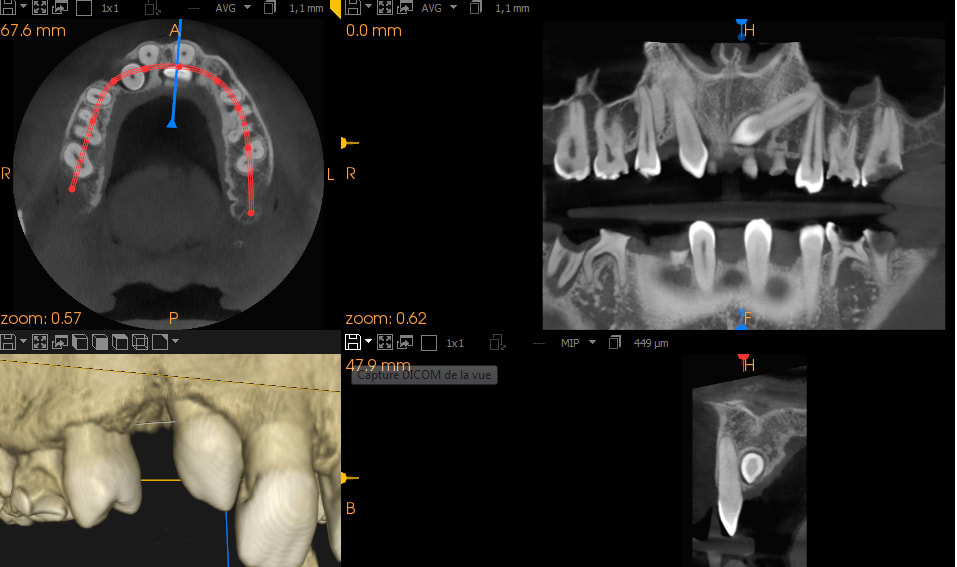

patient adulte avec agénésie multiple. Une cacouille rare au niveau de l'ectoderme.

- os hyper-dense. grosse grosse corticale + un aspect de type 1 partout ( un aspect hein, je suis pas aller voir et c'est un cbct)